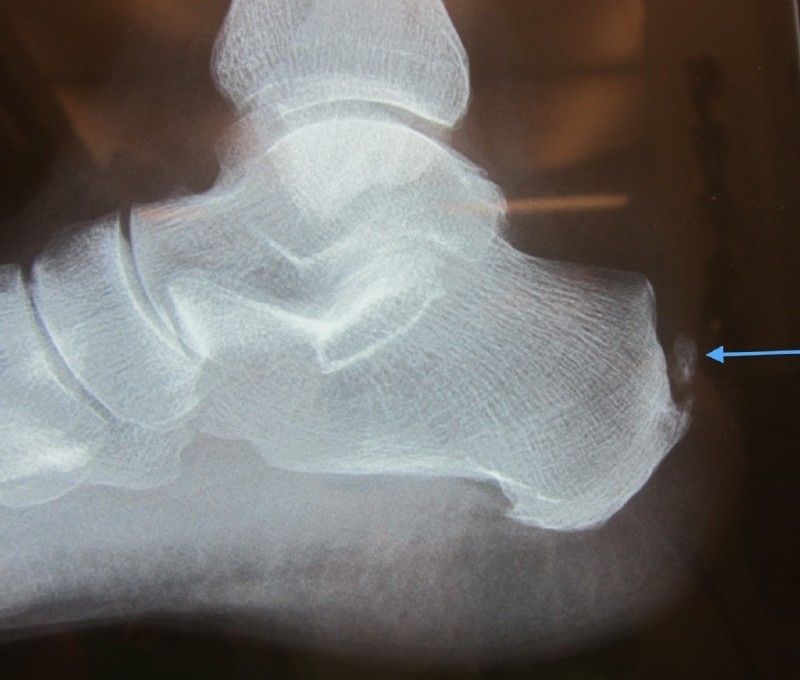

Left: Achilles tendon ossification- upper red arrow, sharp high heel bone – yellow arrow, additional lower calcaneal spur – lower red arrow

Middle: After removal of the ossification (blue arrow) and the high heel bone (yellow arrow)